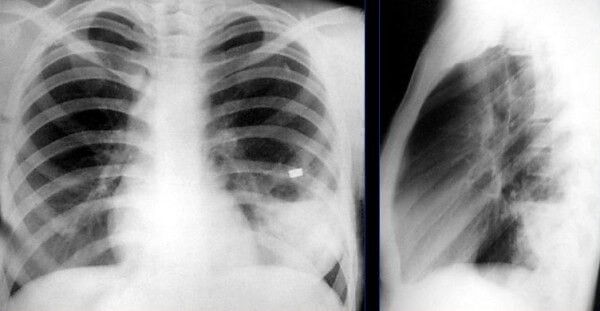

Аспирационная

При аспирационной пневмонии на рентген-снимке видны закупорки бронхов в виде треугольных теней. Диафрагма при этом приподнята.

Снимок при аспирационной пневмонии

Другой тип неинфекционного воспаления лёгочной ткани — аспирационный. Причиной выступает содержимое пищеварительного тракта, попавшее в дыхательные пути. Этот тип патологии характеризуется многообразием симптомов, которые имитируют различные заболевания лёгких.

Как правило, на снимке однородный очаг, контуры относительно чёткие. С целью контроля лечения аспирационной пневмонии рекомендуется проходить повторный рентген.

- Аспирационная форма. Рентген характеризуется треугольными пятнами с однородной структурой, светлыми очагами и приподнятой диафрагмой.